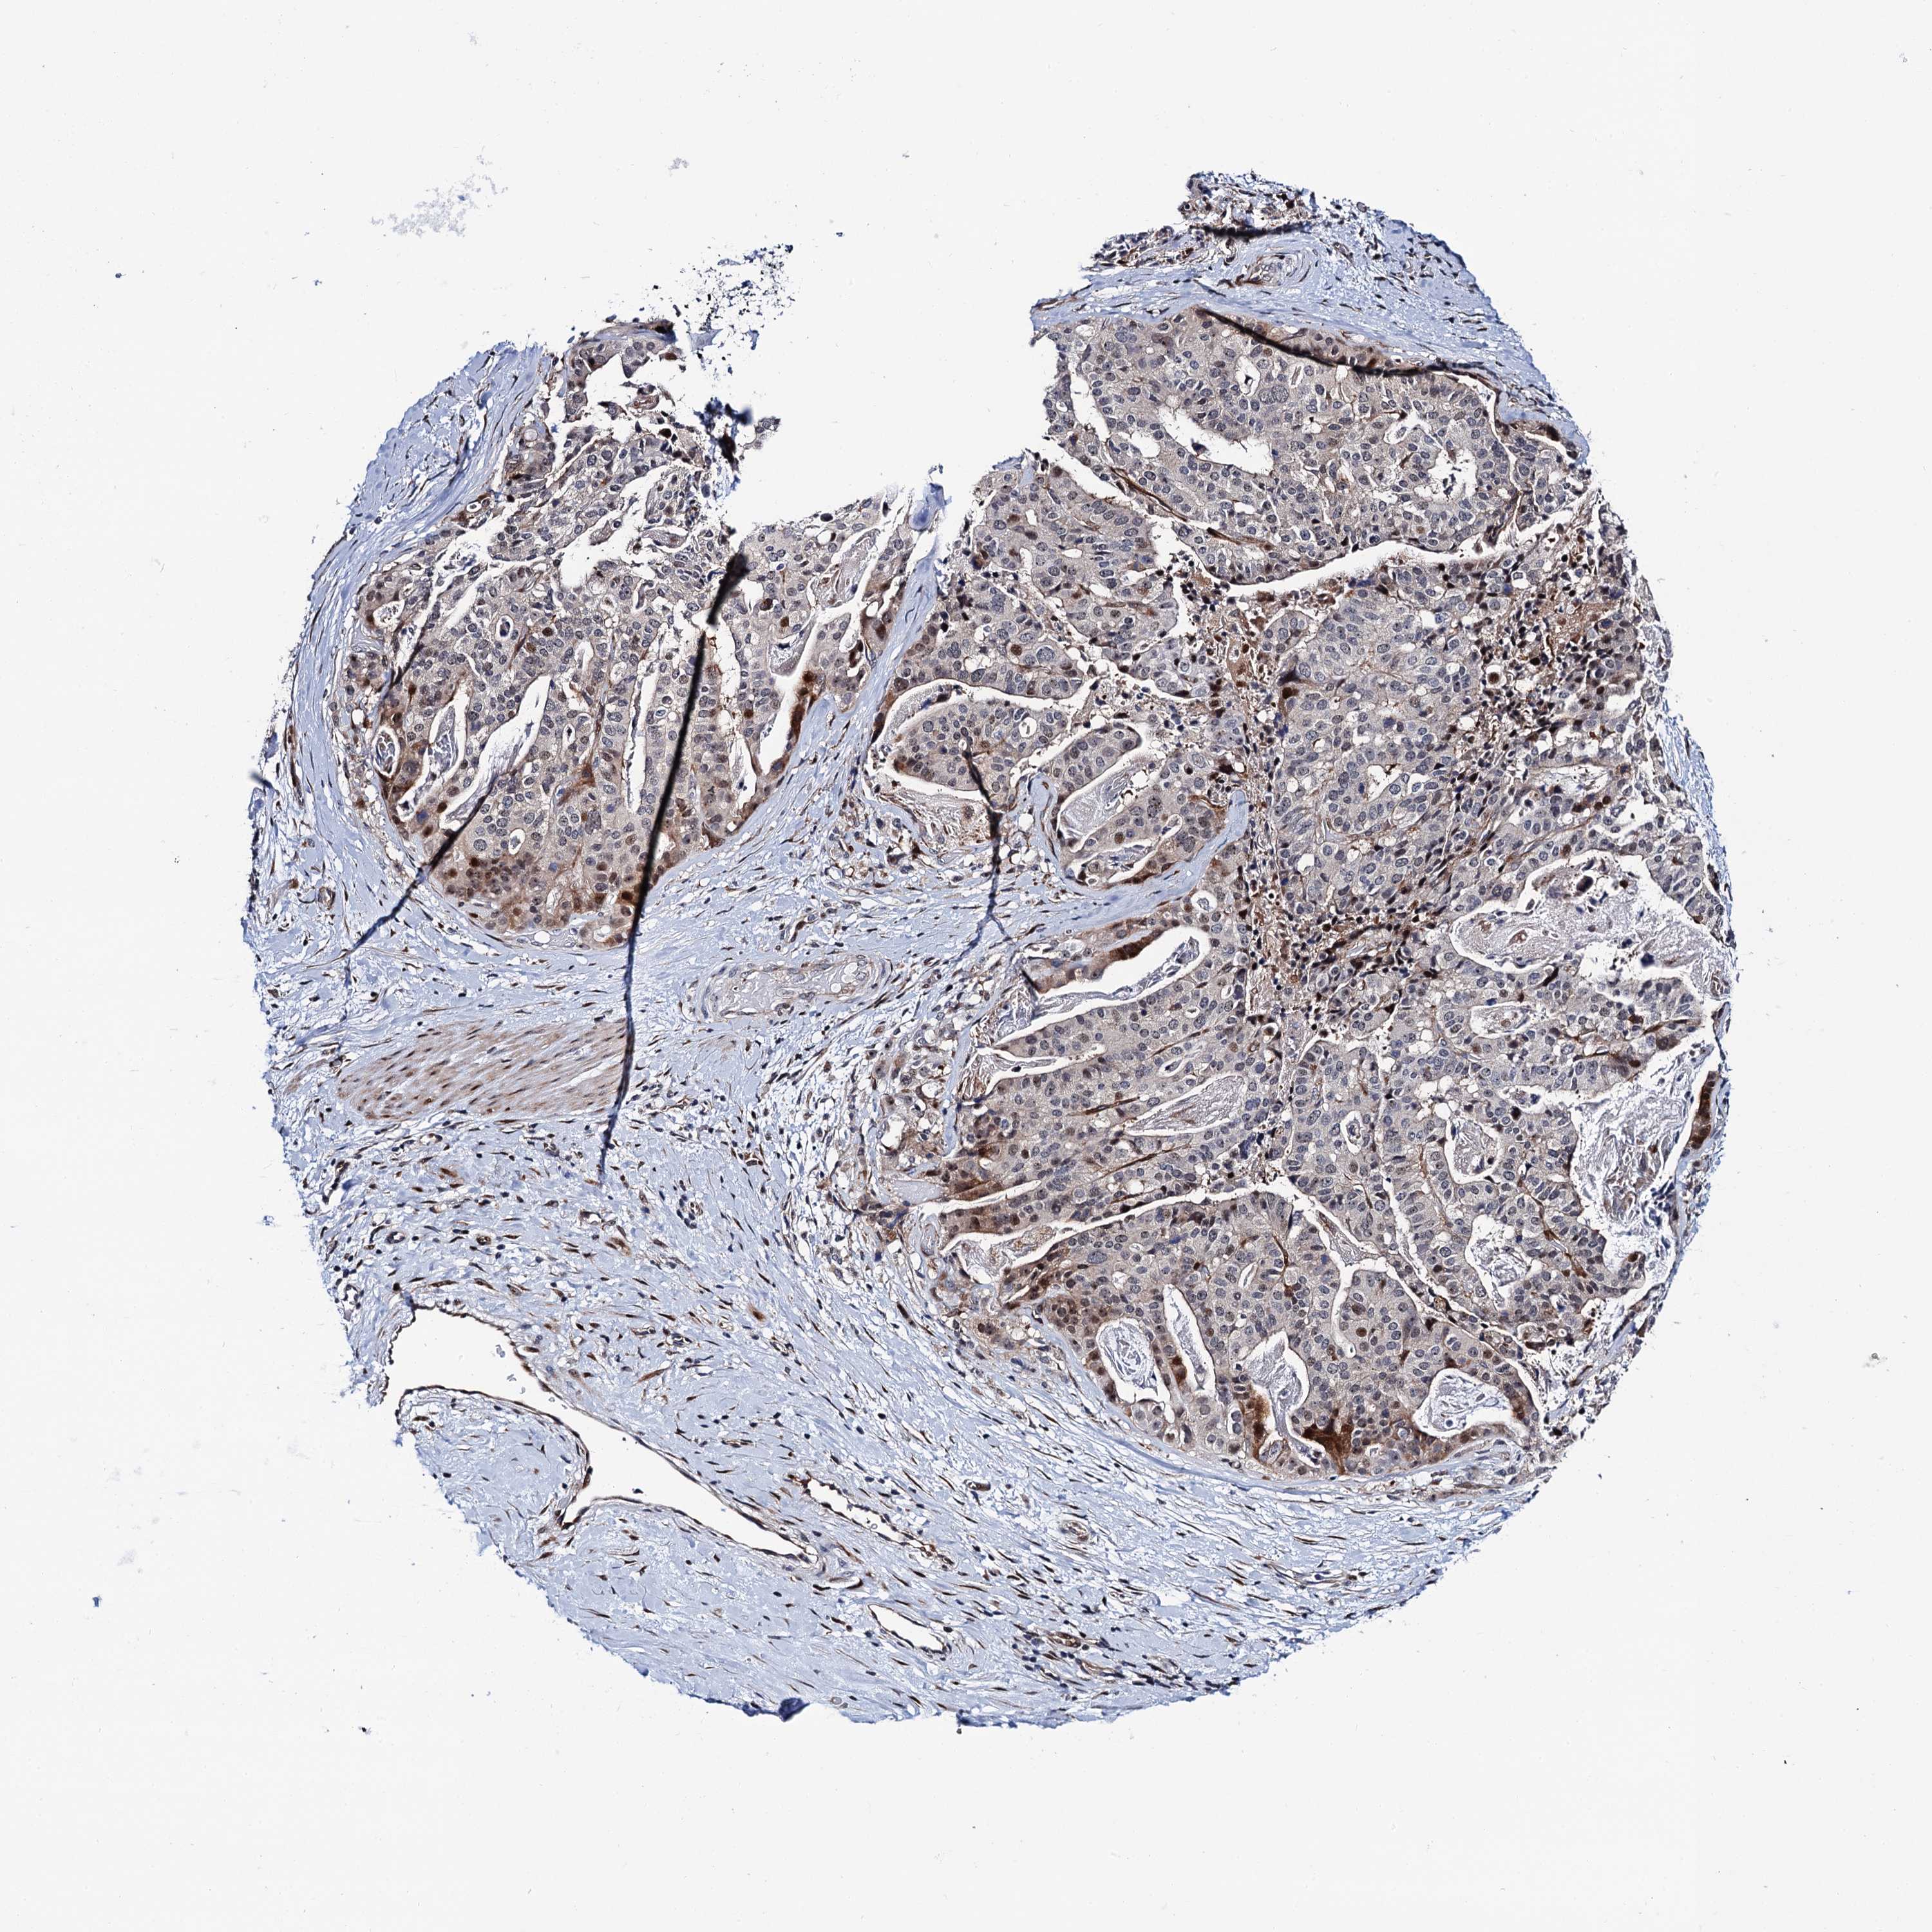

STOMACH CANCER - Protein expressioni

A mouse-over function shows sample information and annotation data. Click on an image to view it in a full screen mode. Samples can be filtered based on level of antibody staining by selecting one or several of the following categories: high, medium, low and not detected. The assay and annotation is described here.

Antibody stainingi

Antibody staining in the annotated cell types in the current human tissue is reported as not detected, low, medium, or high, based on conventional immunohistochemistry profiling in selected tissues. This score is based on the combination of the staining intensity and fraction of stained cells.

Each image is clickable and will lead to virtual microscopy that enables deeper exploration of all samples and also displays staining intensity scores, fraction scores and subcellular localization as well as patient and tissue information for each sample.

Antibody HPA039901

Antibody HPA040006

Staining

High

Medium

Low

Not detected

Intensity

Strong

Moderate

Weak

Negative

Quantity

>75%

75%-25%

<25%

None

Location

Nuclear

Cytoplasmic/membranous

Cytoplasmic/membranous,nuclear

Adenocarcinoma, NOS

Adenocarcinoma, High grade